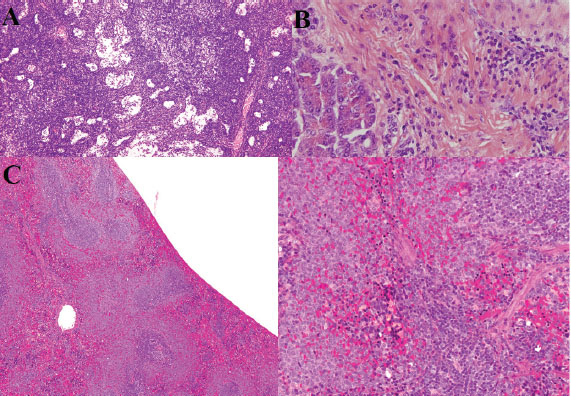

Symptomatic treatment, including fluid therapy and antimicrobial coverage (intramuscular gentamicin sulfate at 15,000 IU), led to the resolution of gastrointestinal signs within 1 week. However, the animal developed persistent anorexia, progressive weight loss, lethargy, and mild ataxia. Chemical immobilization was performed on day 10 post-admission to facilitate advanced diagnostics. Blood samples were collected for serum protein electrophoresis, conventional polymerase chain reaction, and Reverse Transcription Polymerase Chain Reaction (RT-PCR) targeting feline coronavirus (FCoV) (Simons et al., 2005; Wang et al., 2021; Gao et al., 2022) (Supplementary Material S2). Molecular diagnostics confirmed the presence of FCoV RNA in blood samples (Tables 3, 5, and 6 for detailed results and primer sequences; primers were designed based on previously published sequences (Hohdatsu et al., 1991; Stranieri et al., 2020,Böger et al., 2021; Lin et al., 2022). The reference strains included FIPV WSU-79-1146, type II 79-1683, UCD2, UCD4, and FECV UCD (Table 4). Abdominal ultrasonography revealed decreased hepatic echogenicity with possible hepatomegaly, splenomegaly, hyperechoic mesenteric fat, and enlarged mesenteric and sublumbar lymph nodes. Mild abdominal effusion was also noted (Fig. 2B,C). Brain CT showed enhanced meningeal layers and choroid plexus of the fourth ventricle, suggesting meningeal inflammation (Fig. 2A). immunohistochemistry (IHC) and ISH were performed on formalin-fixed paraffin-embedded tissues using established protocols (Stranieri et al., 2020) (Supplementary Material S3). Briefly, IHC employed monoclonal anti-CD68 antibody (1:50; clone KP1, Dako, Denmark) for macrophage identification, anti-cleaved caspase-3 (1:60; Cell Signaling Technology, USA) for apoptosis detection, and broadly cross-reactive anti-ACE2 antibody (1:500; Abcam, UK) for receptor expression (Junqueira et al., 2022). ISH was performed using RNAscope technology (ACD/Bio-Techne, USA) with FIPV-specific spike gene probes (Tortorici et al., 2021; Takeda, 2022; Tortorici et al., 2022). IHC confirmed the presence of FCoV antigen in macrophages within granulomatous lesions, and ISH localized viral RNA to inflammatory foci (Table 7, Fig. 1B,C).

Fig. 1. FCoV presence and ACE2 expression analysis. (A) Successful amplification of the M gene region of FCoV in blood, feces, and tissue samples (305 bp product). (B) In situ hybridization (ISH) for the FIPV spike gene RNA in inflammatory foci. (C) Immunohistochemistry for the ACE2 receptor in endothelial cells using the AEC chromogen.

Fig. 4. Histopathological findings in the lung, heart, liver, and gastrointestinal tract. (A-B) Severe pulmonary edema, hyaline membranes, and vascular thrombosis. (A) Histiocytic, neutrophilic, and lymphoplasmacytic inflammation with multifocal areas of subserosal necrosis with varying degrees. (B) Vascular thrombosis, fibrinoid vasculitis, and syncytial cells. (C–D) Lymphoplasmacytic myocarditis with myocyte degeneration. (C) Hypereosinophilic myocytes and striations. (D) Single apoptotic hepatocyte (600X). (E) Interface hepatitis (piecemeal necrosis), death of hepatocytes at the interface of the parenchyma and connective tissue of the portal zone, accompanied by a variable degree of inflammation and fibrosis. (F–G) Gastric inflammation with neutrophilic vascular aggregates. (F) Jejunum, shortening and loss of epithelial cells with villus fusion and cellular debris along with moderate, multifocal, lympho-plasmacytic-histiocytic inflammation. (G) Ischemia-type colitis showing mucus depletion, patchy atrophic degeneration, polymorphonuclear neutrophil infiltration, and feline coronavirus spike protein in enterocytes and intestinal absorptive cells (Immunohistochemistry, Alkaline Phosphatase (AP), 1000X).

Fig. 5. Histopathology of lymphoid tissues, pancreas, and spleen. (A) Extensive necrosis, vascular thrombosis, cellular debris, lymphoid follicle depletion, and polymorphonuclear neutrophil infiltration. (B) Areas of inflammatory infiltration in the pancreas (hematoxylin and eosin staining, 400X). (C) Depletion of lymphoid follicles in the spleen and reduction of lymphocytes (hematoxylin and eosin staining, 300 dpi).

Fig. 6. Neuropathology and ocular lesions. (A and B) Thorn-shaped astrocytes and pallido-nigral degeneration. (C and D) Vascular necrosis, leptomeningeal inflammation, and perivascular lymphocytic infiltration. (E–H) Corneal inflammation, retinal degeneration, and choroidal vasculitis.